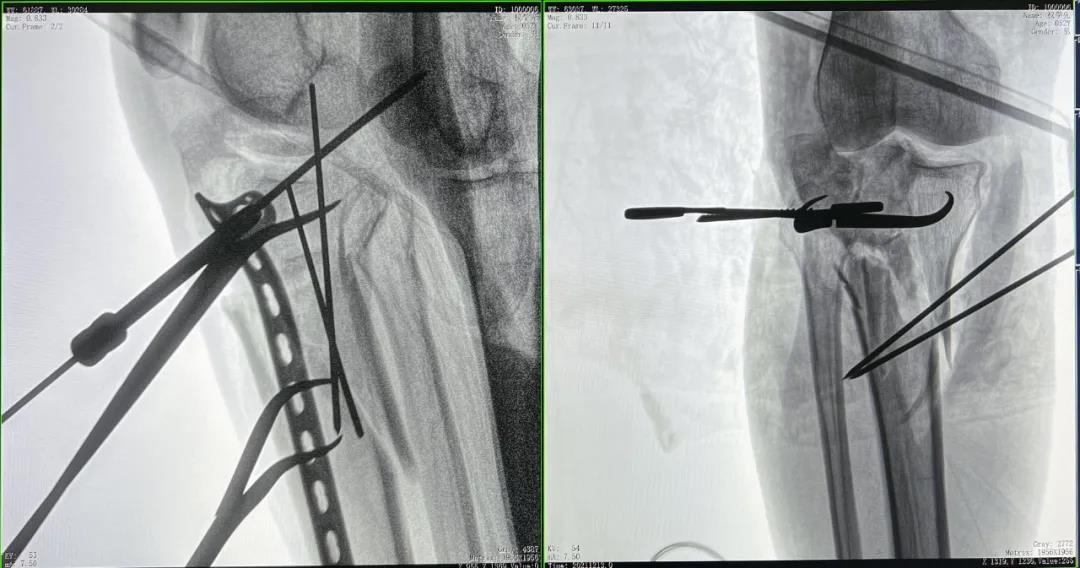

患者2:男性,52歲,脛骨骨折切開復(fù)位鋼板內(nèi)固定術(shù)

術(shù)前CT三維重建影像可見脛骨平臺處粉碎性骨折

優(yōu)質(zhì)的術(shù)中影像輔助螺釘準確植入